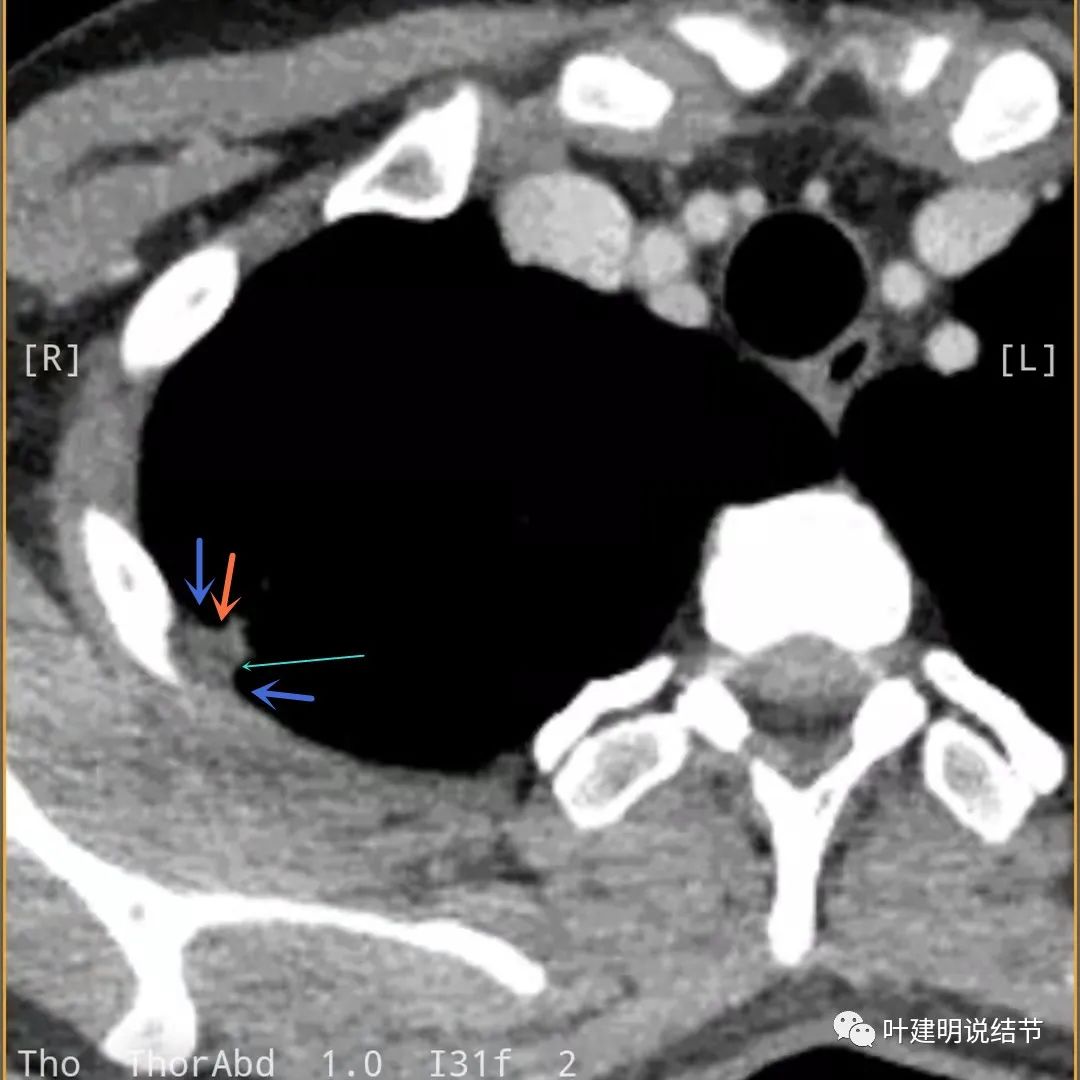

蓝色箭头所指处居然有低密度影,难道是坏死?因为比肌肉密度低,也无强化,况且主病灶的中间也有个低密度的小点状

病灶有明显强化(说明炎性可能性大,如果恶性这样强化,血供丰富,应该倍增速度更快。蓝色箭头示胸膜处低于软组织密度的区域;桔色箭头示病灶边缘平直缺乏膨胀性;黄色箭头示中间的空腔

邻近胸膜处的增厚密度低于肌肉组织,病灶强化明显且均匀

此层也见明显的低密度区域(天蓝色箭头)